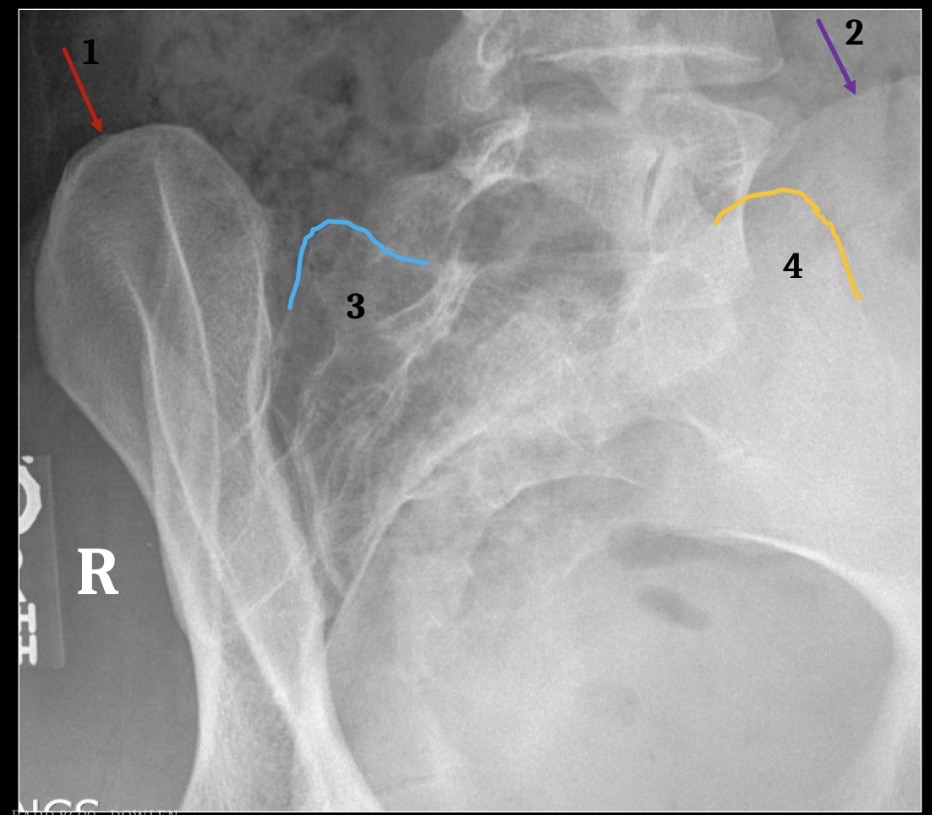

1

Brest

3

Fat deep to abdominal muscle

5

Gluteal crease

6

Lateral margin left psoas muscle

7

Hemidiaphragm

8

Gastric air bubble

4

Inferior articular process

Superior margin of pedicle

Superior articular processes

Vascular channel

Interlaminar space

Lamina

Superior endplate, anterior margin

Superior endplate, posterior margin

9

Accessory tubercle

11

Mammillary Process